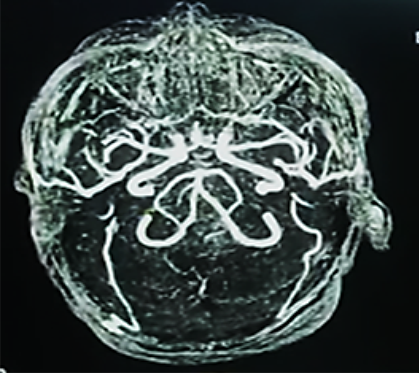

Aun a pesar del tratamiento instaurado de forma multidisciplinaria, permaneció con tendencia a la hipertensión arterial de difícil manejo, bajo analgo-sedación, en asistencia respiratoria mecánica, nuevamente con vasodilatadores endovenosos y medidas de protección cerebral (en primera línea); a las 2 semanas de hospitalización con más deterioro neurológico disminución de los reflejos del tallo cerebral, con tendencia a la bradicardia e hipertensión arterial extrema (probable síndrome de Cushing), se realiza una nueva TAC de cráneo que muestra importante edema cerebral con borramiento de las cisternas peri mesencefálica, compatible con un deterioro rostro caudal (Figura 4a, b)